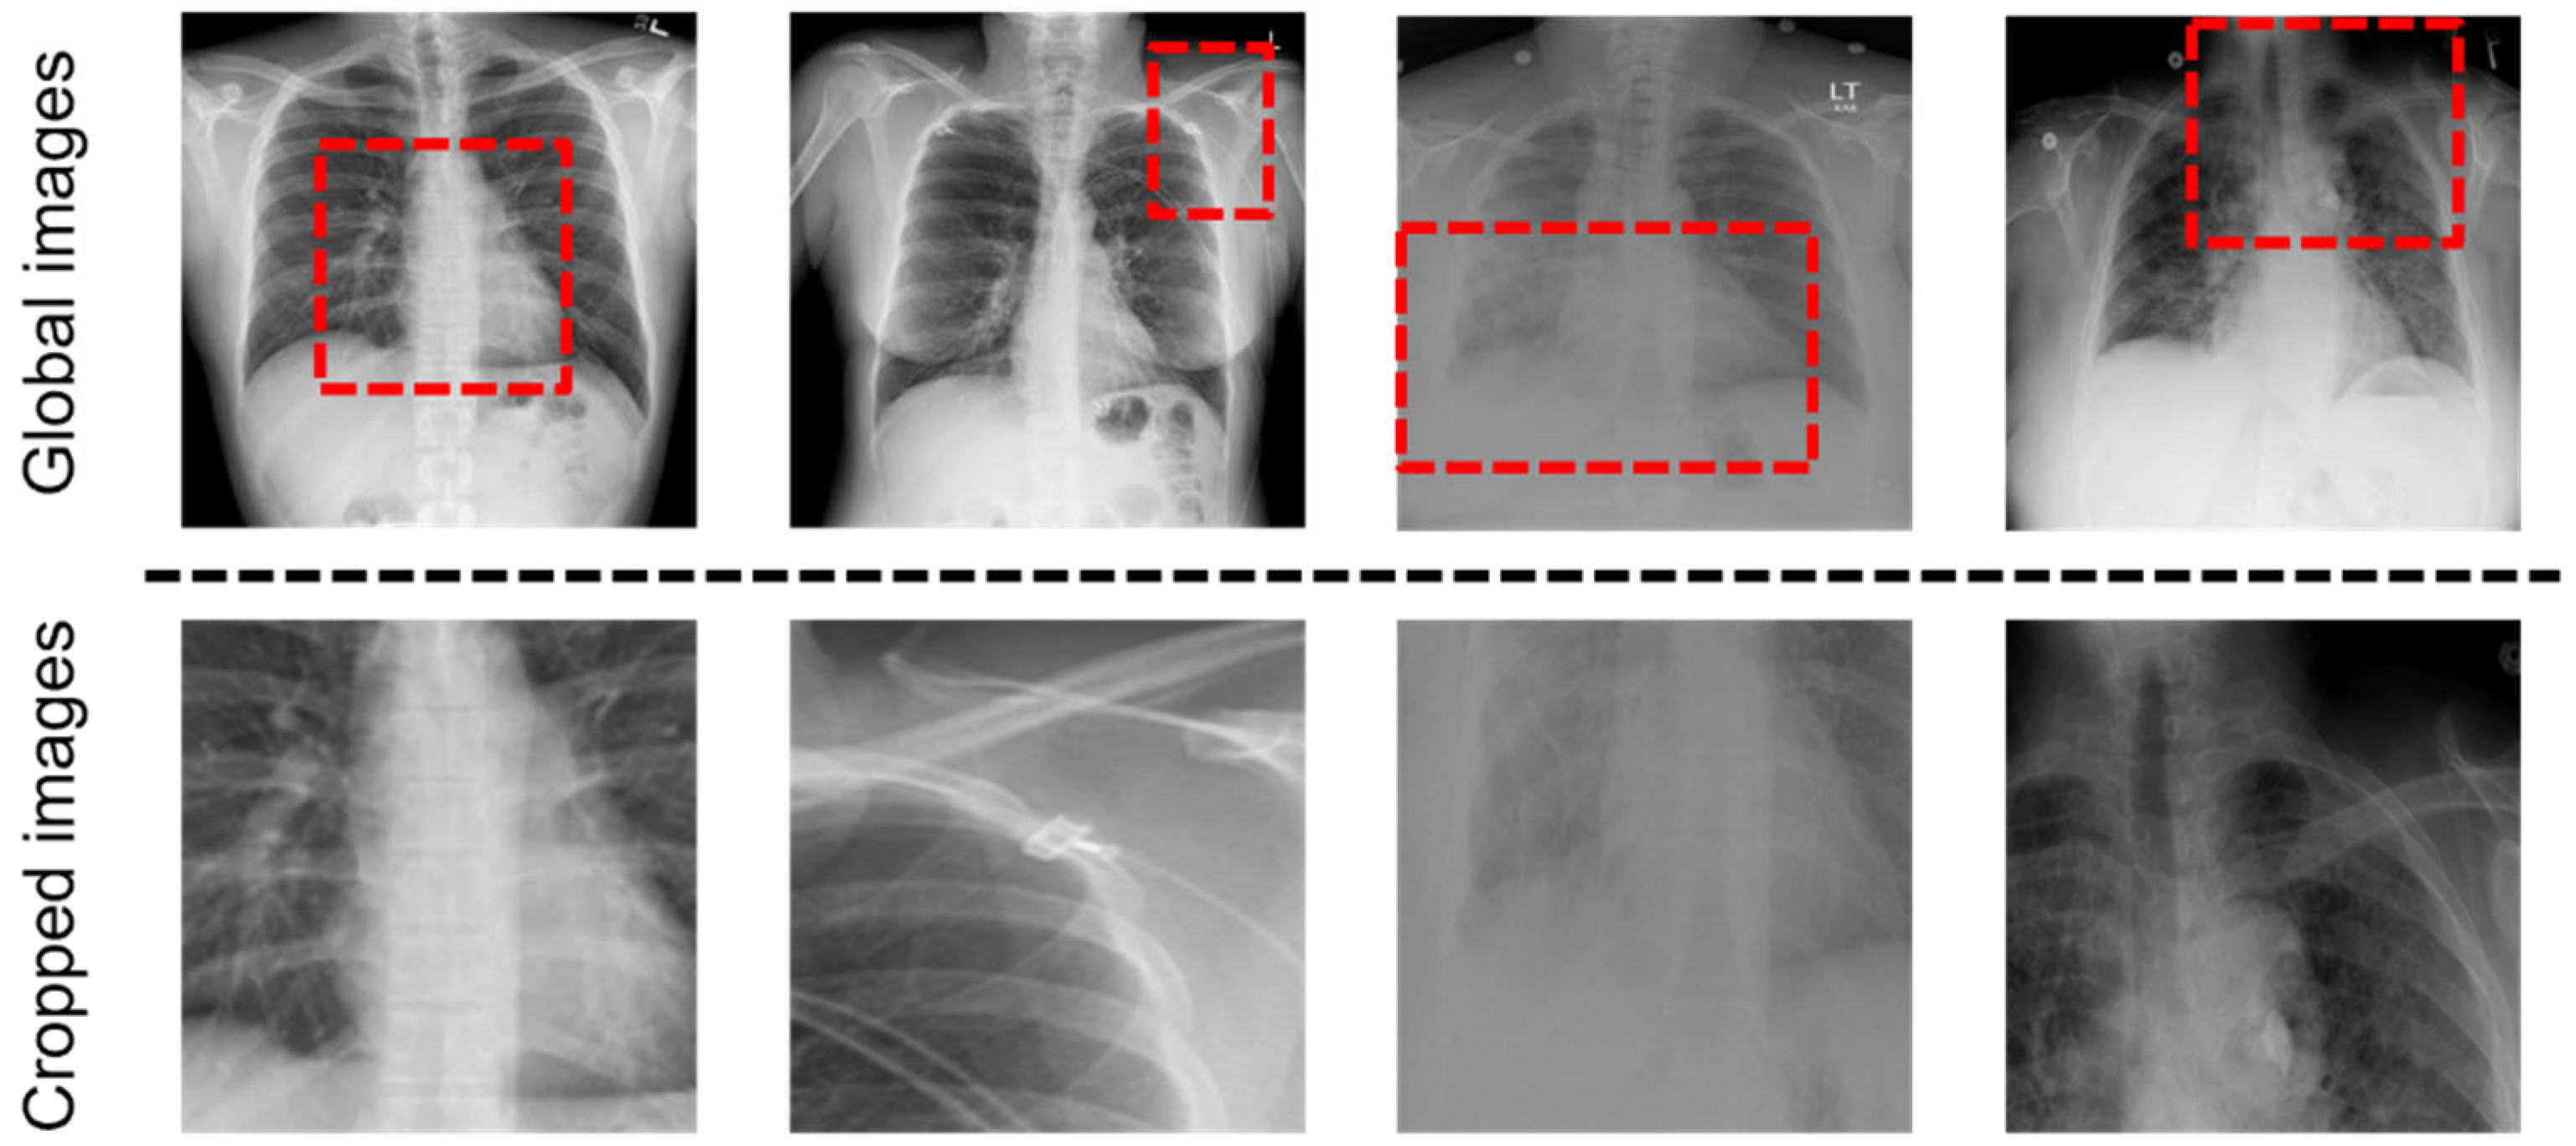

Figure 2.

Example of input images of the GLVE. (Top): Global Radiology images, the input of the global visual extractor. We used a dashed box to indicate the region to be cropped. (Bottom): Cropped and resized images from corresponding images, used as the input of the local visual extractor.

There are problems that occur when learning only from these global images: (1) Since the size of the lesion area may be small or the location may not be predicted, the global visual features may include the information on noise. (2) There are various capture conditions such as the patient’s posture and body size [13]. To address the problems, the local visual extractor is added with the global visual extractor, and the features extracted from the local visual extractor are concatenated to the global visual features. As shown in Figure 3, we crop the important part of the image with the last layer of the global visual extractor, resize it to the same size as the image and use it as the input of the local visual extractor. We create a binary mask to locate the region by applying thresholds on the feature maps. In the th channel of the last CNN layer of the global visual extractor, denotes the activation values of spatial location , where , K = 2048 in Resnet-101, and represents the coordination of the feature map. The attention heat map is defined as: